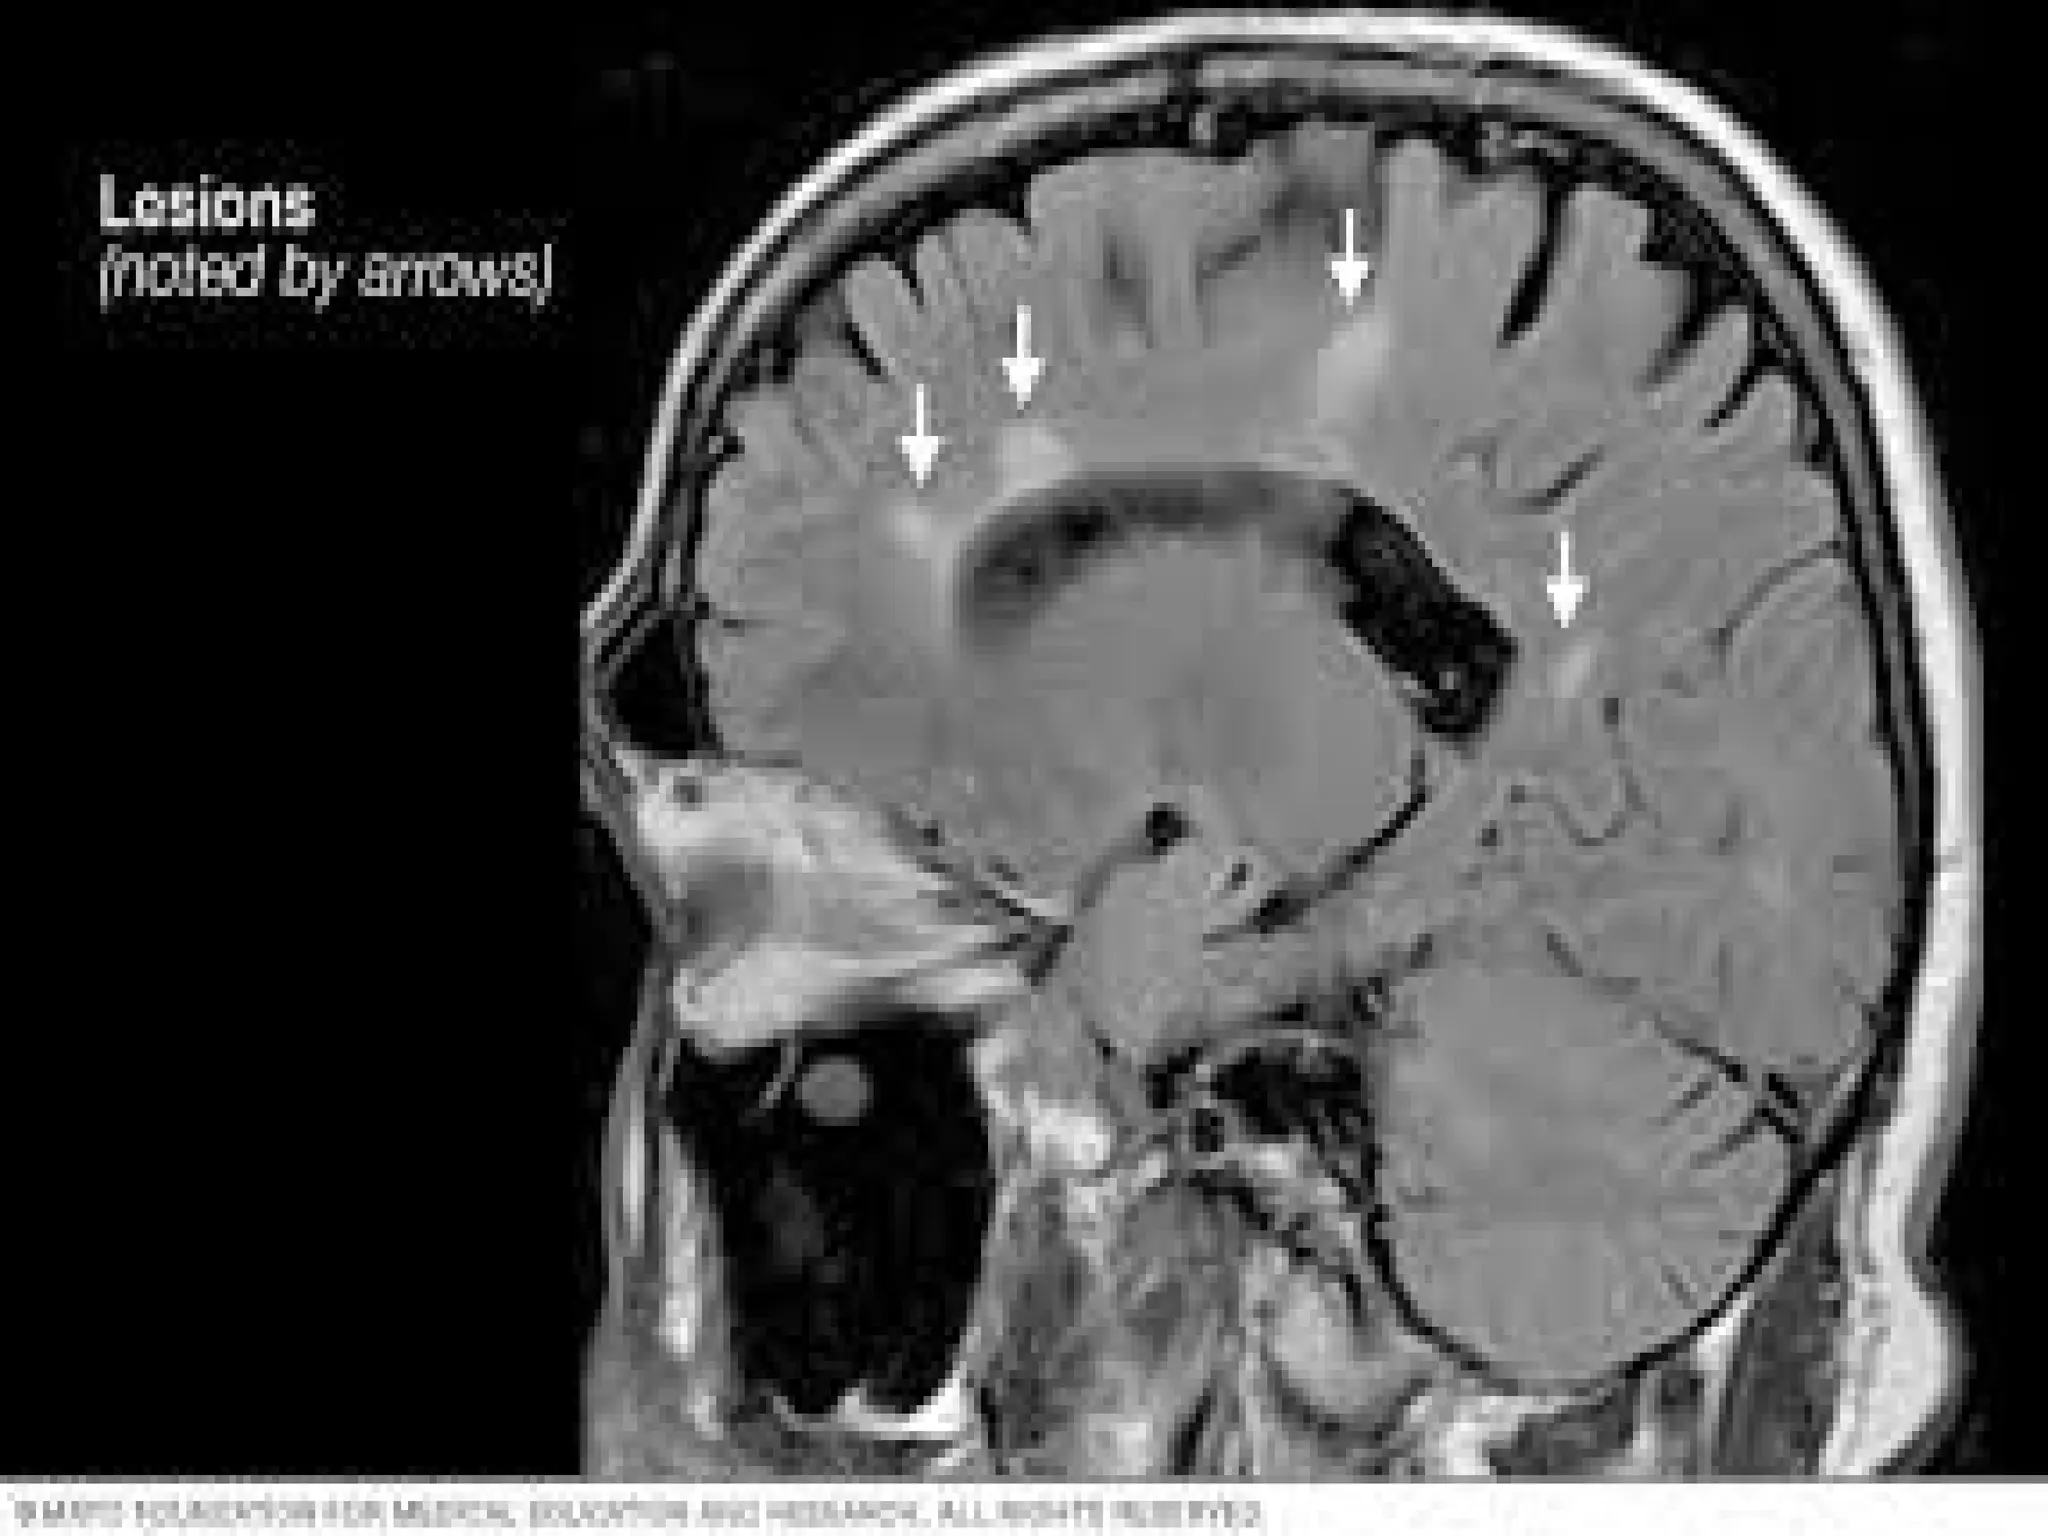

Results: Repeated attacks on the axon, the

surrounding myelin sheath eventually causes

scarring or plaques that interrupt or even

block nerve impulses, causing progressive

cognitive/physical disability

• #9 Although scientists are still working out the details of the immune attack in MS, the basic steps involved appear to be as follows: Misguided immune cells—called T cells—cross the blood-brain barrier (BBB) into the CNS. The BBB, which is thought to consist of walls of capillaries in the CNS, usually prevents or slows the passage of undesirable substances (e.g., disease-causing organisms) from the blood into the CNS. These T cells release chemicals that rally other immune system forces that attack the myelin coating around the nerve cells, as well as the cells that manufacture myelin. This attack causes inflammation and then destruction. The nerve fibers themselves also come under attack. Once the myelin and nerve fibers have been damaged, nerve signals are slowed or stopped. MS lesions (damaged areas as seen on MRI) form, with hardened scars or plaques that may impair normal myelin repair processes.